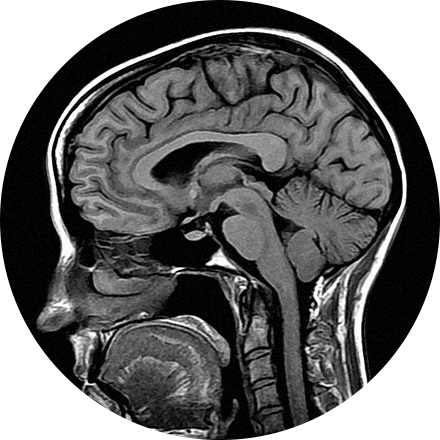

NeuroQuant

NeuroQuant (NQ) is an artificial intelligence (AI) tool that calculates the volume of different substructures of the brain and compares those to a large normative age- and gender-matched database to determine whether the degree of brain volume loss is statistically significant for patient age. This can be used to improve the early detection of Alzheimer’s Disease (AD) or other neurodementia syndromes. NeuroQuant-MS is used to calculate the volume, number, and location of plaques in patients with multiple sclerosis. The software highlights new, enlarging, or shrinking plaques. This allows for accurate tracking of disease status over time. NQ can also be used to detect the location of a seizure focus in patients with epilepsy. It is also used in brain trauma patients or to assess brain development. Neuro-Quant has both MRI and CT applications. Other NeuroQuant-based AI tools in development include volumetric quantification and characterization of brain tumors.